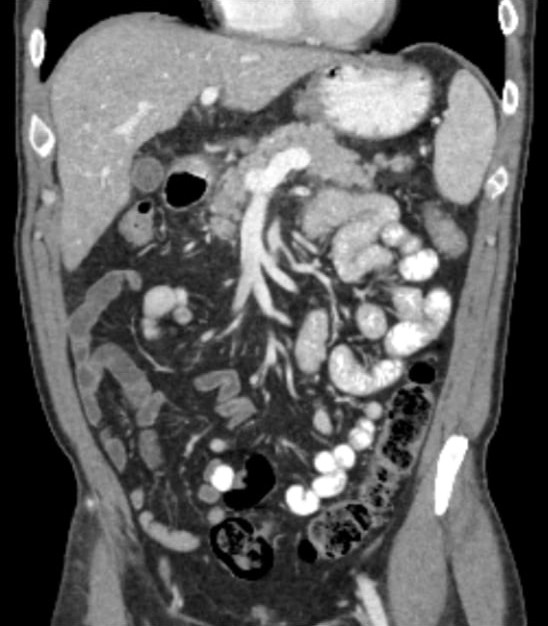

A non-iodinated 'blood-pool' agent that remains in the vascular system for minutes, enabling unprecedented interrogation of blood vessels and the liver.

+ Extended Imaging Window

+ No Mixing Artifacts

+ High BMI Patient Solution

Cardiovascular Disease

Trauma Triage

Liver Lesion Characterization

Vivid, prolonged, full-vascular enhancement

Conventional Iodine

Poor and inconsistent opacification with rapid washout